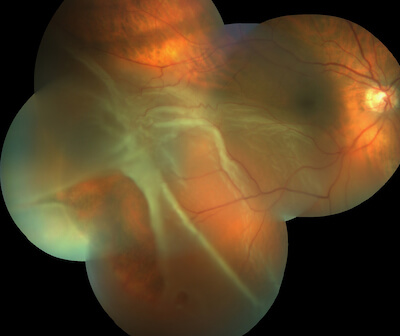

This photo montage shows a retinal detachment. The white areas of the retina are the detached portion, as it is elevated above the back surface of the eye. If left untreated, this may cause permanent impaired vision. Some early signs of retinal detachment are flashes of light and a sudden onset of floaters.